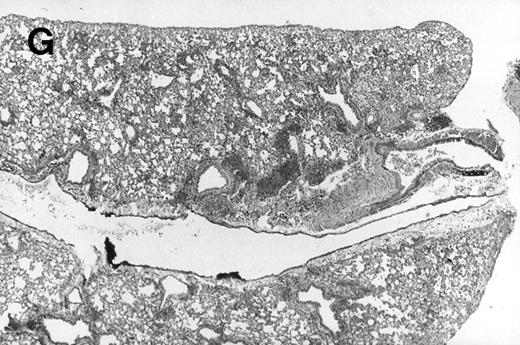

Allogeneic transplanted mice (B10.BR → CBA) with GVHD and, as controls, allogeneic transplanted mice without GVHD and syngeneic transplanted mice (B10.BR → B10.BR) were infected intranasally with HSV-1 at 12 weeks after transplantation. As an additional control, age-matched normal CBA mice were infected as well. Histological examination of lungs was performed in mock-infected mice and in mice at day 7 after infection. Allogeneic transplant recipients with GVHD showed increased pathology (Fig 1). Scores reflecting the periluminal histopathologic changes were significantly higher (P = .05; Student's t-test) in allogeneic transplant recipients with GVHD, when compared with control mice (Fig 2). The periluminal histopathologic scores were also higher in allogeneic transplant recipients with GVHD, when compared with normal CBA mice, at days 4, 10, and 14 after infection (data not shown). No significant differences were observed in the scores reflecting the parenchymal histopathologic changes (data not shown). Because the results in syngeneic transplanted mice were very similar to those in allogeneic transplanted mice without GVHD, the latter, which are the most appropriate control for procedural effects and for the effect of GVHD, and normal CBA mice, were used as controls in further experiments.

Allogeneic transplant recipients with GVHD showed increased pathology. Photomicrographs of lung sections stained with hematoxylin and eosin show evidence of increased pathology in infected allogeneic GVHD mice. (A) Normal CBA, mock-infected, original magnification × 25; (B) normal CBA, mock-infected, original magnification × 100; (C) normal CBA, infected, original magnification × 40; (D) normal CBA, infected, original magnification × 100; (E) allogeneic GVHD, mock-infected, original magnification × 10; (F) allogeneic GVHD, mock-infected, original magnification × 75; (G) allogeneic GVHD, infected, original magnification × 10; (H) allogeneic GVHD, infected, original magnification × 100.